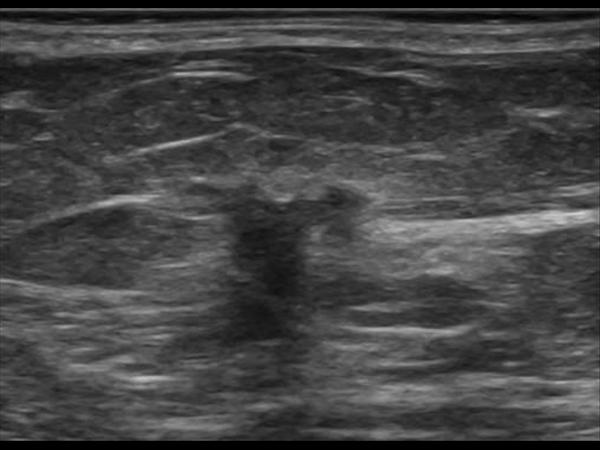

Ung thư vú

Ung thư vú - Ảnh 2

Ung thư vú - Ảnh 3

Ung thư vú - Ảnh 4

Ung thư vú - Ảnh 5

» Thông tin: Nữ giới – 71 tuổi.

» Lâm sàng: Khối tuyến vú.